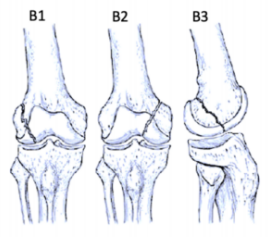

股骨遠(yuǎn)端骨折分型

股骨遠(yuǎn)端骨折可根據(jù)骨折模式、部位和膝關(guān)節(jié)受累情況進(jìn)行分型 ,AO/OTA分型常用于對(duì)這些骨折進(jìn)行分類。在每個(gè)類別中,骨折可根據(jù)復(fù)雜性和移位程度進(jìn)一步分類,對(duì)于與全膝關(guān)節(jié)置換術(shù)(TKA)相關(guān)的假體周圍股骨遠(yuǎn)端骨折,基于骨折移位和TKA股骨假體完整性的Lewis和Rorabeck分型(1997年)是最常用的分型:

A型:關(guān)節(jié)外骨折

不累及關(guān)節(jié)面

B型:部分關(guān)節(jié)內(nèi)骨折

累及部分關(guān)節(jié)面但保持一定的關(guān)節(jié)匹配性

C型:完全關(guān)節(jié)內(nèi)骨折

關(guān)節(jié)面完全破壞